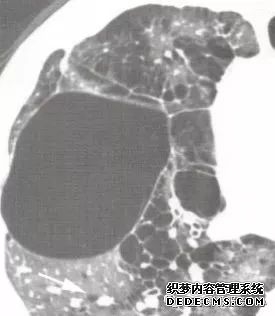

肺内淋巴结的CT表现特点及与病理对照